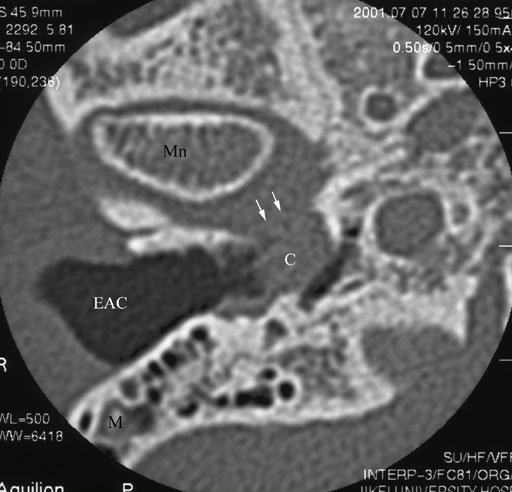

画像所見としては両側外耳道骨部に軟部濃度病変を認める.外耳道骨部骨壁に明らかな浸食性変化は見られない.内側は鼓膜に達するが,鼓室内進展は見られない.軟部濃度病変内に明らかな石灰化は見られない.画像所見としての特異性は余り高くはないが,両側性であること,疼痛をともなうこと,またCT上,慢性アレルギ―性鼻副鼻腔炎の所見を伴うなどの臨床像と合わせると”閉塞性角化症”が考慮される.

• 図4

剥離角化上皮の堆積という点において閉塞性角化症と外耳道真珠腫は同じ病態と考えられる場合も多い.臨床的な外耳道真珠腫は(外耳道内において剥離上皮を外側に排出するサイクルの機能低下の生じてくる)比較的高齢者に多く,慢性的な耳の鈍痛と耳漏を訴える点において異なる.CT上は閉塞性角化症では骨浸食性変化は見られず,ときに外耳道骨部の平滑な拡大を来すのに対して,外耳道真珠腫では高度に骨浸食性変化を示す(図4).また,閉塞性角化症では両側性に病変を認める場合がある.